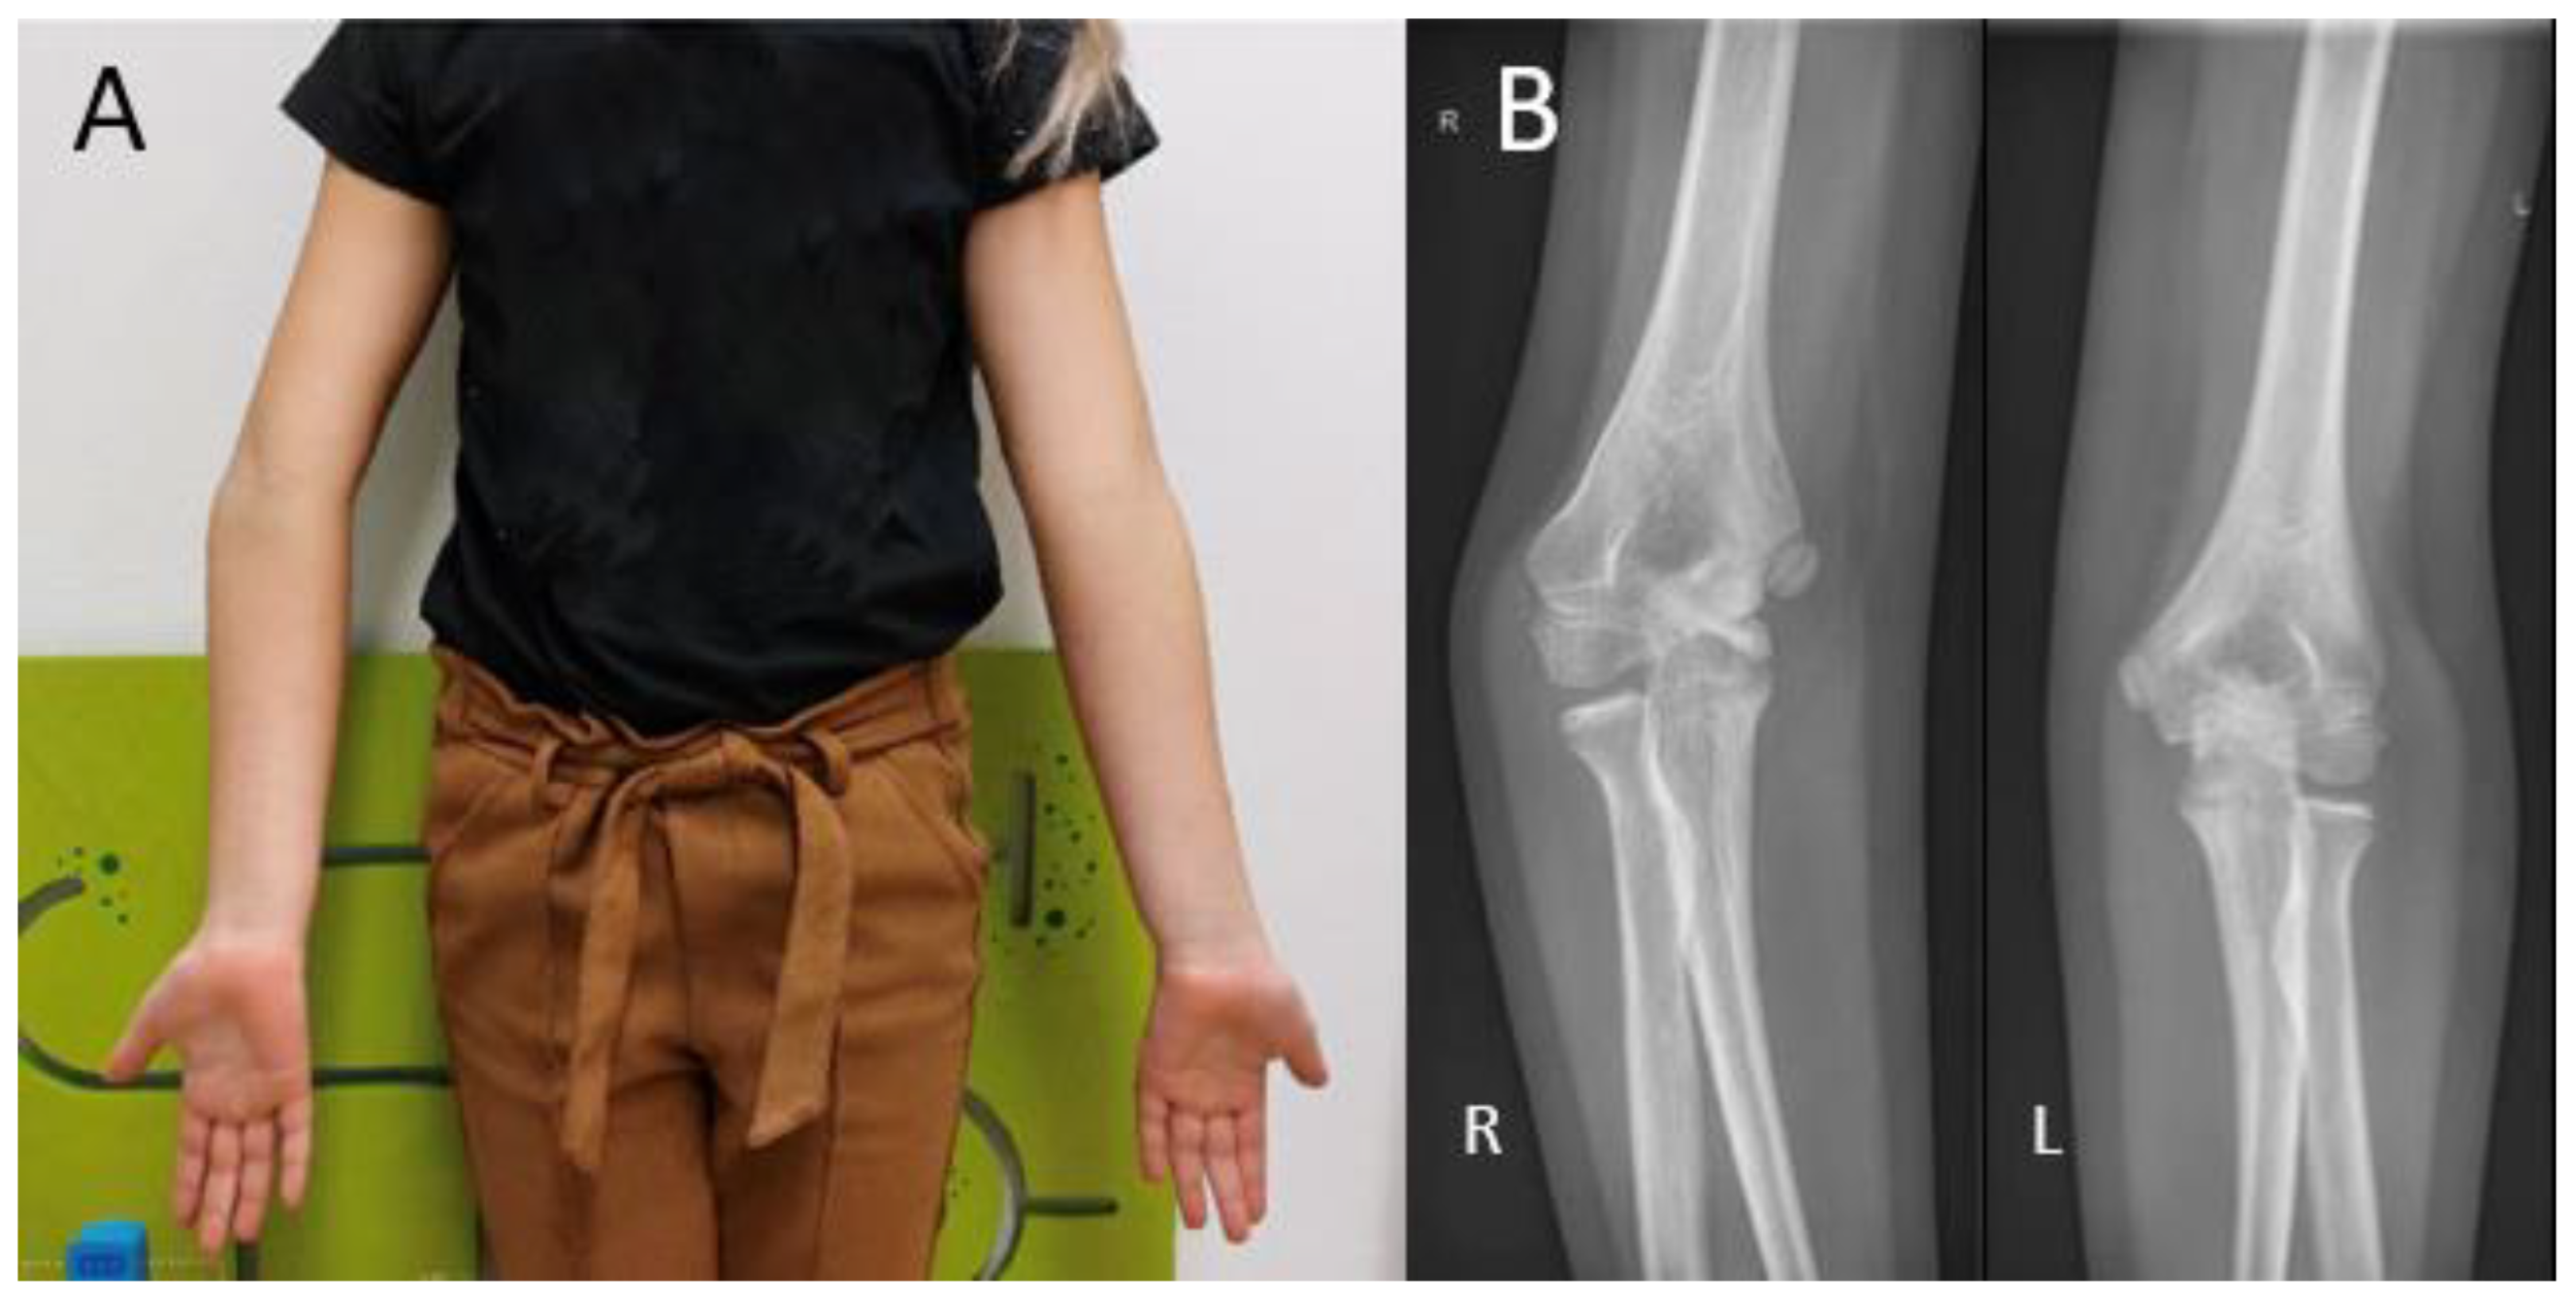

Proximal radial fractures represent up to 10% of all pediatric elbow fractures [29,30]. The mechanism of injury is usually a fall on an outstretched hand, combined with a compressive valgus force across the elbow joint. Despite the occurrence of these fractures around the growth plate, premature physeal closure occurs in about 1.5% of patients [30]. Growth has more impact, however, in congenital radial head dislocations (Figure 5). Although rare in absolute numbers, it is the most common congenital elbow abnormality, accounting for up to 10% [31]. Dislocations occur bilaterally in most cases. Around 70% of dislocations occur posteriorly, followed by anterior and lateral dislocations, occurring around 15% each [31]. With frequent dislocations, the normal anatomical relation of the radial head with the capitellum and the proximal radioulnar joint (PRUJ) during growth may be lost. Without the pressure of the radial head onto the capitellum during growth, a malformation of the radial head with loss of concavity occurs, making reduction in longstanding cases impossible [31]. Patients are generally presented with a painless mass at visual inspection or palpation. Elbow flexion may be slightly decreased in the case of an anterior dislocation, and extension may be slightly decreased in the case of a posterior dislocation. Additionally, DRUJ alignment may be lost, resulting in decreased ROM during pronation and supination [31]. A lateral elbow radiograph is often sufficient to diagnose this condition. Herein, the extent of radial head deformation is a reliable guideline in the decision of whether to operate on a patient [32]. If the radial head is more dome-shaped and has lost all its concavity, surgery tends to be unsuccessful.

Figure 5. (A) A 17-year-old boy with congenital anterior radial head dislocations of the right arm. (B) A 16-year-old girl with congenital posterior radial head dislocations of the left arm, accompanied by a symptomatic elbow contracture. The girl was treated conservatively with a static progressive elbow flexion brace.